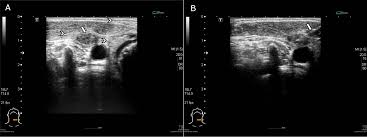

Ultrasound Of Neck Lymph Nodes How To Do It And How Do They Look Sciencedirect

Ultrasound Of Neck Lymph Nodes How To Do It And How Do They Look Sciencedirect from ars.els-cdn.com

Chapter 5 Ultrasound Characteristics Of Benign Vs Malignant Cervical Lymph Nodes Sciencedirect

Chapter 5 Ultrasound Characteristics Of Benign Vs Malignant Cervical Lymph Nodes Sciencedirect from ars.els-cdn.com